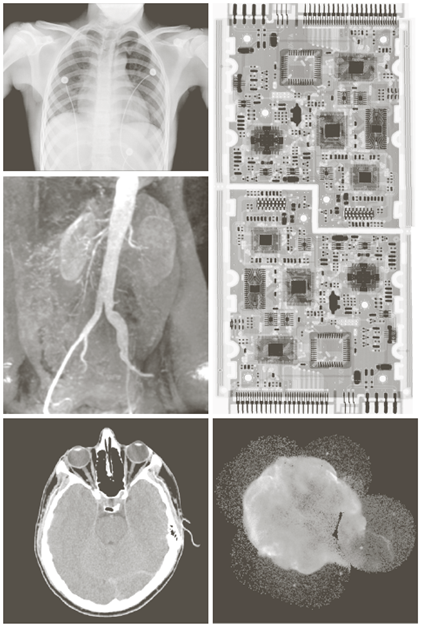

X-ray image

Visual band image – 영상처리에 의한 품질검사

a) 회로 기판